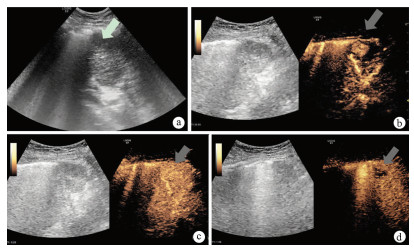

Expert consensus on the imaging diagnosis of hepatic echinococcosis

Radiology of Infection Sub-branch, Radiology Branch, Chinese Medical Association, Committee on Radiology of Infectious, Radiology Branch, Chinese Medical Doctor Association

2021, 37(4): 792-797. DOI: 10.3969/j.issn.1001-5256.2021.04.014

Abstract(1244) HTML (604) PDF (2065KB)(121)

Abstract:

Echinococcosis is a zoonotic disease with global distribution and has become an issue seriously affecting public health around the world. Imaging technology plays an important role in the early diagnosis, preoperative evaluation, and treatment outcome monitoring of hepatic echinococcosis. At present, no consensus has been reached on the imaging diagnosis of echinococcosis, which brings difficulties in the learning and training of imaging professionals and the standard diagnosis and treatment of echinococcosis in clinical practice. For this reason, Beijing YouAn Hospital, Capital Medical University, and The First Affiliated Hospital of Xinjiang Medical University organized the radiologists engaged in infection and inflammation from several hospitals to reach a consensus on the basis, principles, and criteria for the imaging diagnosis of echinococcosis and the differential diagnosis of echinococcosis, with reference to international guidelines, related articles, the latest research findings in China and globally, and the methodological requirements for the establishment of guidelines and standards in evidence-based medicine, so as to provide a clear diagnostic basis for clinicians in the clinical application of hepatic echinococcosis imaging.